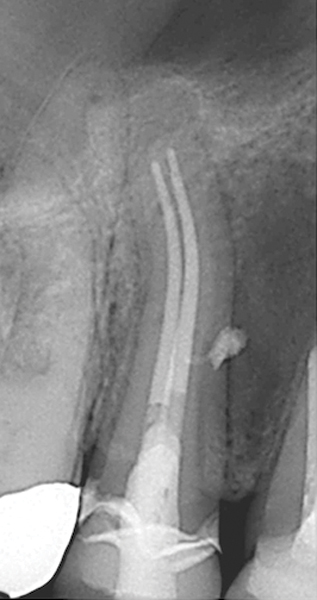

Fig 15. Preoperative radiograph. Courtesy of Dr. Sam Kratchman.

Figure 15

Fig 16. Post apicoectomy. Courtesy of Dr. Sam Kratchman.

Figure 16

Fig 17. Retropreps and isthus filled. Courtesy of Dr. Sam Kratchman.

Figure 17

Fig 18. 20-month follow-up with BC putty shows complete healing. Courtesy of Dr. Sam Kratchman.

Figure 18